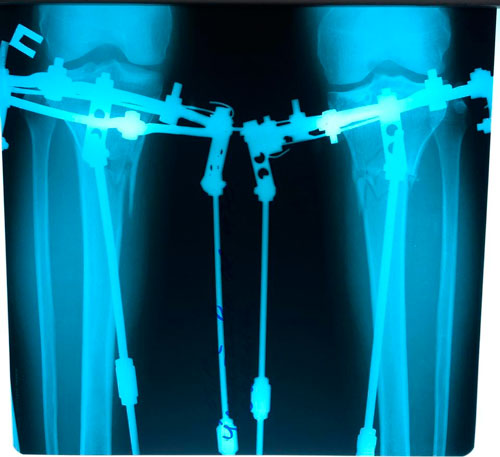

Рентген и фото на фиксации

Вложения

IMG_2964-03-05-19-09-46.JPG

IMG_2963-03-05-19-09-46.JPG